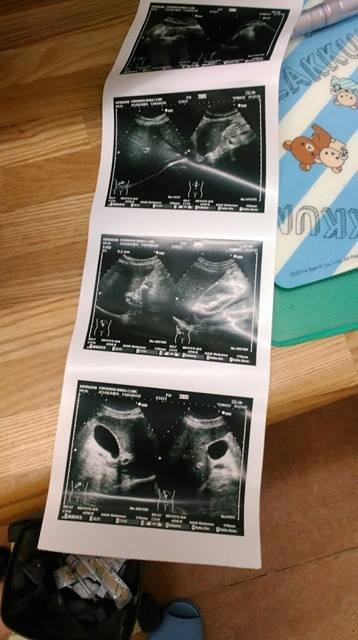

これを見ても全く私にはわからないのですが、胆のうも肝臓もきれいな物らしく、単なる胃痛というありがたいのやらありがたくないのやらわからない診断で、胃薬を貰ってくるだけという結果に終わりました。